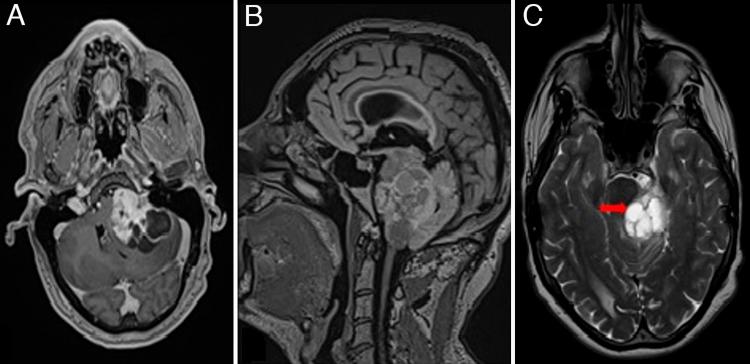

The authors report a case of a 44-year-old patient who developed severe herpes meningitis a few days after removal of a large cystic vestibular schwannoma.

作者报告了一例44岁患者,该患者在切除一个大型囊性前庭神经鞘瘤几天后发生了严重的疱疹性脑膜炎。